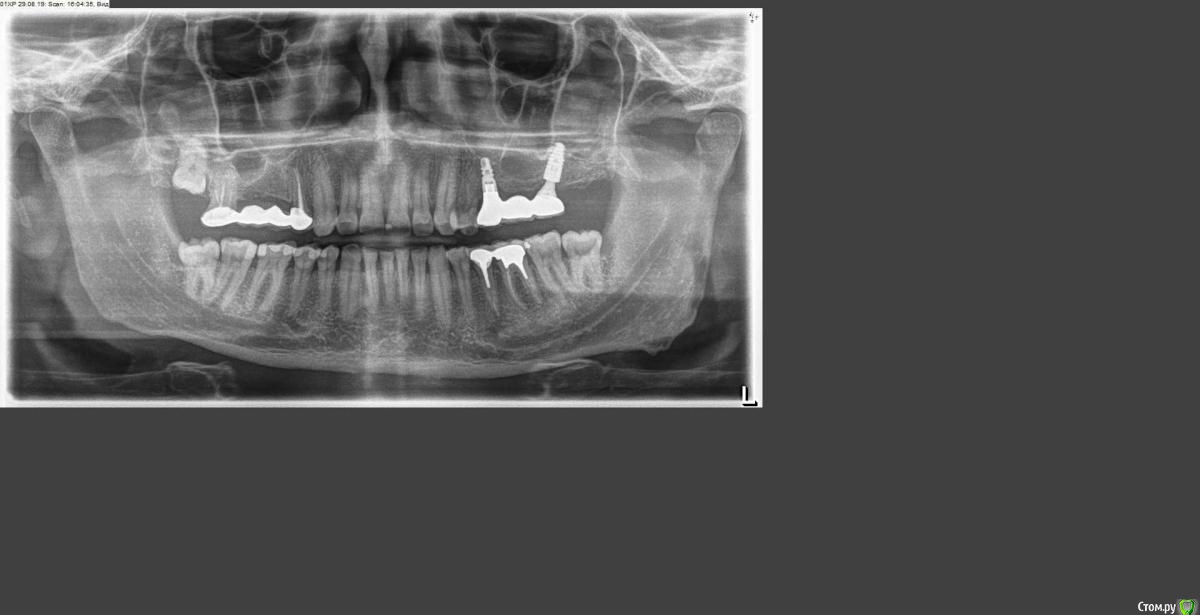

Самарец Опубликовано 30 января, 2020 Поделиться Опубликовано 30 января, 2020 Добрый день! После установки моста на верхних имплантах, антагонисты 35 и 36, после полуторагодовалого отдыха без нагрузки стали сопротивляться.Проявлялось сначала дискомфортом после поедания твердой пищи. В настоящее время - образовался свищ в верхней части десны в районе 36 зуба. На приеме у доктора - промыли, заложили лекарство и вроде все успокоилось. Проблемное место - указано стрелкой в корне 36 зуба. Опухлость десны прошла. Думаю что это все временно. После консультаций у докторов при обострении предлагаются 3 варианта:1. Откинуть лоскут в районе 36 зуба и прочистить проблемное место с лекарством. 2. Разъединить коронку 35 от 36 зуба, удалить 36 зуб и через 2 месяца вкрутить имплант. Коронку 35 зуба обточить.3. Выдернуть 35 и 36 и после заживления вкрутить 2 импланта (это мое предположение) . Посоветуйте пожалуйста уважаемые господа что бы вы рекомендовали в данной ситуации? Заранее благодарю!P.S. Коронке около 14 лет. Ссылка на комментарий